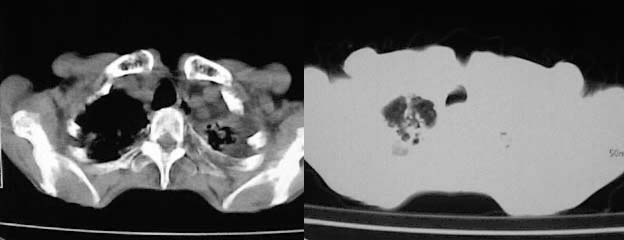

以下是引用zjzjr在2008-5-2 14:39:00的发言:[br]支持双侧继发型肺结核,左侧胸膜肥厚,慢性支气管炎伴间质纤维化.

以下是引用有风的日子在2008-5-2 12:13:00的发言:[br][emb10][br][br]肺ca?有病理支持吗?[br][br]我看更象是肺tb并支扩、间质性肺炎。最好拿个病理结果来,不然这点影像资料诊断肺ca是难以服人的![br][br]至于主动脉瘤的诊断问题,国外认为≥4.0cm就可诊断了,国内对此诊断标准更为严格。患者升主动脉明显增粗,即>4cm。你诊断个升主动脉扩张并不为过!